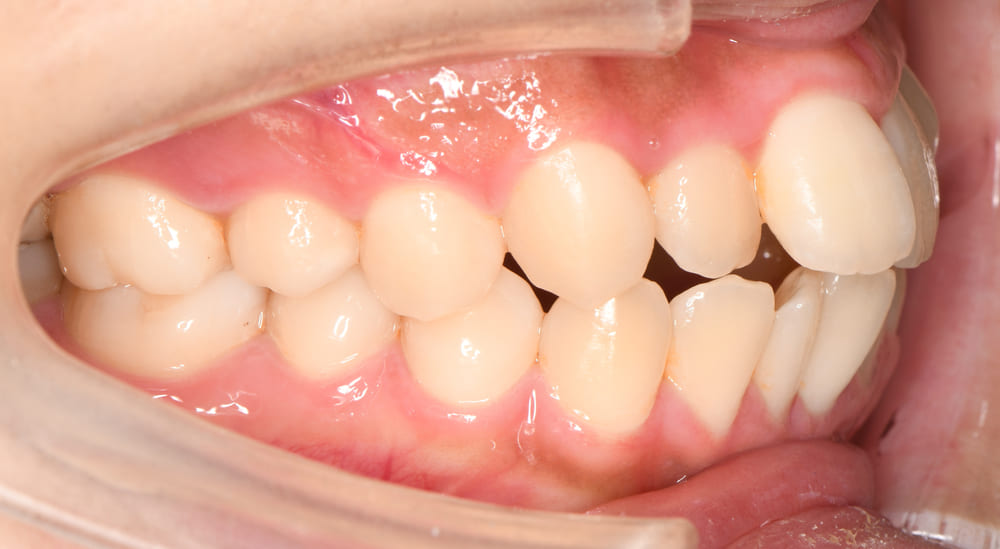

右側からの口腔内写真です。上下顎の前歯が著しく前方に傾斜していることがお分かりいただけると思います。